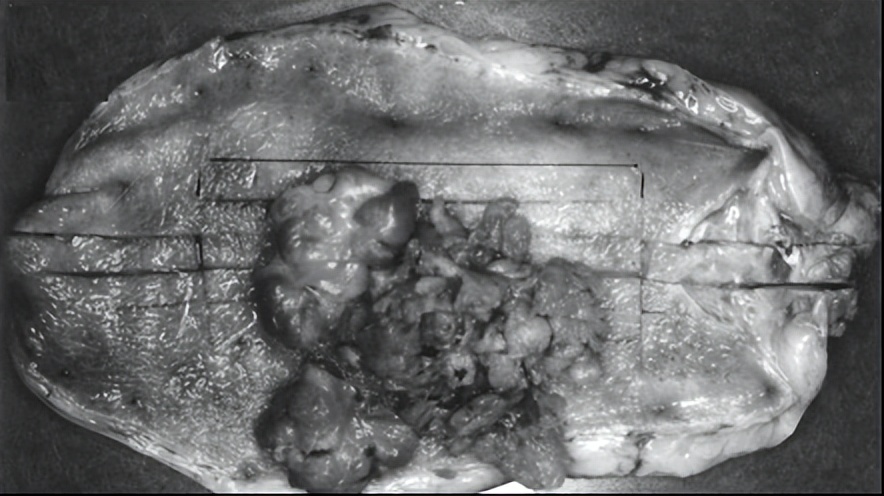

胆固醇性息肉是胆固醇沉着症的表现形式之一,约占胆囊息肉总数的62-90%,无恶变潜能,病理基础为胆囊黏膜局部脂代谢紊乱。胆固醇息肉是树状息肉样病变,呈独特的花椰菜状结构,质脆蒂细,易与黏膜分离。

图片来源:胆石症研究中心,侵权删除